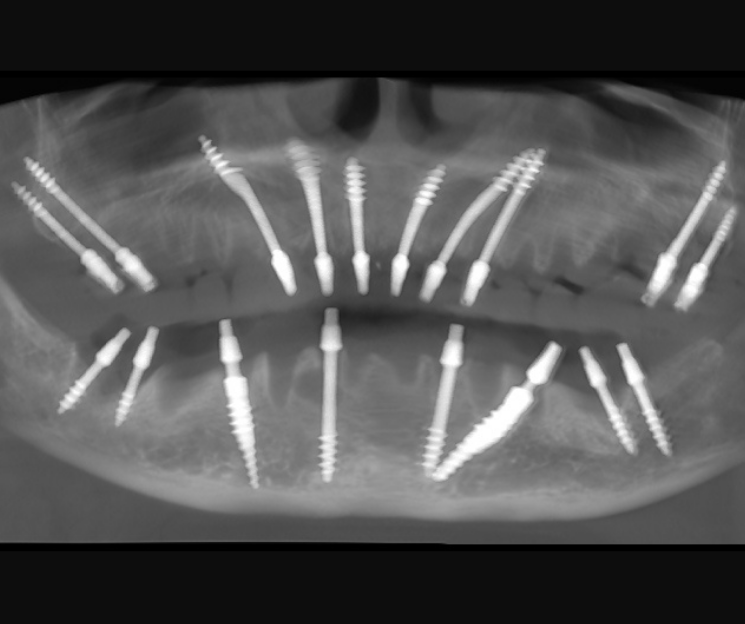

Clínica Dental especializada en la CDMX, Tijuana, Toluca, Cuernavaca, San Luis Potosí.  Colocamos  implantes dentales monofásicos de carga inmediata, también conocidos como implantes de una sola pieza. Somos una alternativa más rápida, estética y menos invasiva frente a los implantes tradicionales.

*Procedimiento: Colocación de implantes dentales monofásicos. A diferencia de los tradicionales (bifásicos), estos son de una sola pieza (tornillo y pilar integrados), lo que permite, colocar el implante y la prótesis provisional en una sola intervención o en un plazo de 3 días.

Más de 20 años de experiencia en casos complejos.

Trayectoria: Más de 15,000 implantes colocados y más de 2,000 pacientes con arcos completos rehabilitados.